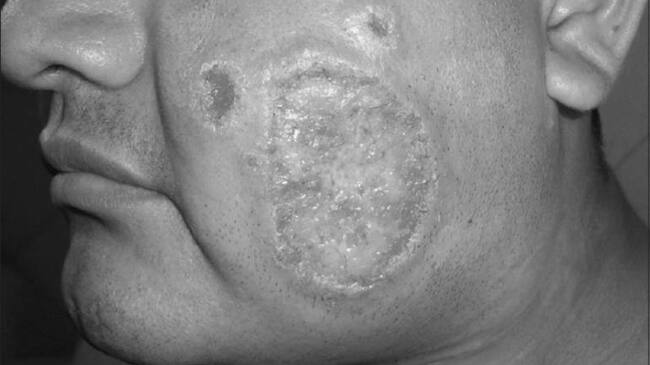

(Foto http://www.odermatol.com/)

La leishmaniasis es un conjunto de enfermedades zoonóticas y antroponóticas causadas por protozoos del género Leishmania. Las manifestaciones clínicas de la enfermedad van desde úlceras cutáneas que cicatrizan espontáneamente, hasta formas fatales en las cuales se presenta inflamación grave del hígado y del bazo.